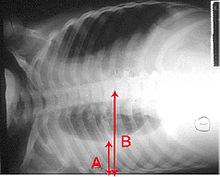

Pleural effusion Anteroposterior Chest X-ray of a pleural effusion. The A arrow shows fluid layering in the right pleural cavity. The B arrow shows the normal width of the lung in the cavity

When a pleural effusion has been determined to be exudative, additional evaluation is needed to determine its cause, and amylase, glucose, pH and cell counts should be measured.